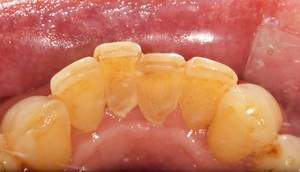

スケーリング

治療前

治療後

| 年齢 | 49歳・男性 |

| 主訴 | 歯石を取りたい |

| 治療内容 | 全顎歯石除去 |

| 治療期間 | 60分 |

| 費用 | 約2,000円(保険適用) (2023年5月現在) |

| リスク・副作用 |

・歯ぐきの炎症が強いと歯石を取る際に出血することがあります。 ・処置後に歯がしみることがあります。 ・歯と歯の間に隙間ができるので、息が漏れ発音しにくいと感じることがあります。 ・歯ぐきの炎症が軽減すると歯ぐきが引き締まり、歯が長く見えることがあります。 |

| 治療方針 | 久しぶりの歯科医院で歯石が硬く多量でした。歯ブラシ指導も併せて行いました。 歯ぐきの中の見えない部分にも歯石が多量に付着しているので今後は縁下歯石除去(SRP)を行なっていく予定です。 |

| 担当者所見 | 歯石がなくなり歯ぐきが改善するとことにより、しみやすいことをお伝えしました。セルフケア指導としては1本ずつ丁寧に磨くことをお話しさせて頂きました。 柔らかめの歯ブラシで斜め45度に歯と歯ぐきの境目に当て磨くこと、洗口剤の使用を提案しました。 |